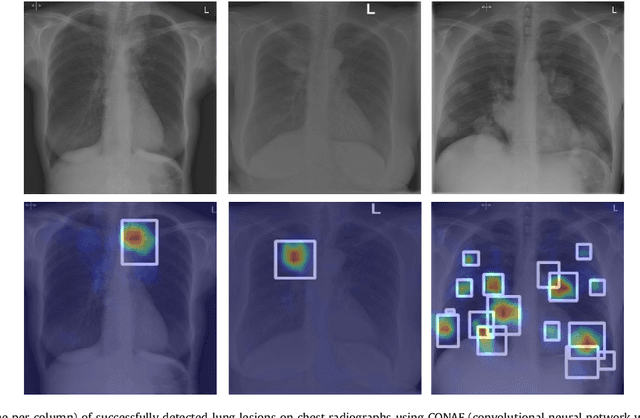

Abstract:Machine learning approaches hold great potential for the automated detection of lung nodules in chest radiographs, but training the algorithms requires vary large amounts of manually annotated images, which are difficult to obtain. Weak labels indicating whether a radiograph is likely to contain pulmonary nodules are typically easier to obtain at scale by parsing historical free-text radiological reports associated to the radiographs. Using a repositotory of over 700,000 chest radiographs, in this study we demonstrate that promising nodule detection performance can be achieved using weak labels through convolutional neural networks for radiograph classification. We propose two network architectures for the classification of images likely to contain pulmonary nodules using both weak labels and manually-delineated bounding boxes, when these are available. Annotated nodules are used at training time to deliver a visual attention mechanism informing the model about its localisation performance. The first architecture extracts saliency maps from high-level convolutional layers and compares the estimated position of a nodule against the ground truth, when this is available. A corresponding localisation error is then back-propagated along with the softmax classification error. The second approach consists of a recurrent attention model that learns to observe a short sequence of smaller image portions through reinforcement learning. When a nodule annotation is available at training time, the reward function is modified accordingly so that exploring portions of the radiographs away from a nodule incurs a larger penalty. Our empirical results demonstrate the potential advantages of these architectures in comparison to competing methodologies.